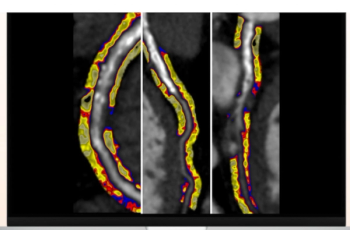

The AI software Viz AAA offered a sensitivity of 87.5 percent in detecting abdominal aortic aneurysms on contrast-enhanced CT, according to new retrospective research presented at the American Roentgen Ray Society (ARRS) conference.